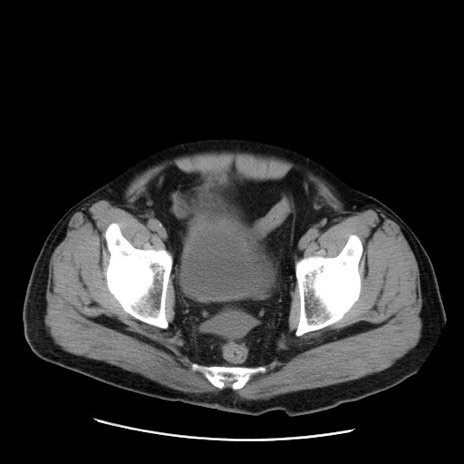

症例20(横断像)

【症例】 60歳代男性

【主訴】 腹部膨満、嘔吐

【現病歴】5日前頃より倦怠感を認め食事量減少し4日前の朝嘔吐、食事摂取困難となった。 3日前近医受診し点滴施行され整腸剤などを処方された。 当日他院を受診し、腹部膨満著明、炎症反応の上昇(CRP10.8、WBC11200)あり、紹介受診となる。

【身体所見】 意識JCS1 受け答えがはっきりしないBP 111/57mHg、 P 67bpm、、BT35.2°C、SpO2 97%(RA)、 腹部:膨隆、打診で鼓音あり、全体的に圧痛有り、腸蠕動音(-)、反跳痛ははっきりせず。

【データ】WBC 11400、CRP 14.20